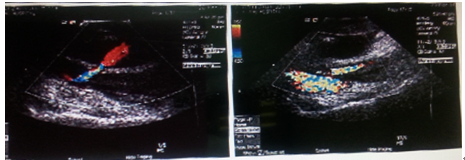

患者术后第2天透析1次,肾功Cr:501umol/L。纠正心衰后BNP由35000pg/ml降为10940pg/ml。血常规RBC 2.52×1012;Hg 82g/L。查体:左侧透析穿刺部位血肿形成,可闻及杂音,下肢较右侧肿胀,皮温可。患者一般状况可。于术后第3天最后透析后拔除左侧股静脉穿刺管,穿刺点呈动脉喷出状,压迫包扎后行超声检查;提示:股动脉前方可见一4.0×5.0×2.0cm 液性暗区,与股动脉相通,交通口为3mm,考虑为假性动脉瘤,瘤体较大,压迫效果差,建议凝血酶微创介入治疗,否则可能会致动脉瘤体积逐渐增大。股静脉血液流速较慢,不排除血栓形成。因患者股静脉怀疑血栓形成,持续压迫会加重血栓及肺栓塞风险,如果行凝血酶微创介入治疗假性动脉瘤,也具有凝血酶发生动脉、静脉及凝血酶过敏的并发症。经和家属分析病情,讨论治疗方案的风险,家属同意行凝血酶微创介入治疗。

患者在超声引导下于假性动脉瘤体内注入凝血酶液8ml(每毫升凝血酶液喊凝血酶220u),10s后假性动脉瘤交通口完全闭塞,瘤体内局部血肿形成(图4)。于1小时左右患者出现寒战过敏反应,给予地塞米松、氢化可的松等抗过敏治疗,症状缓解。于微创治疗12h 后患者出现意识丧失,血压80/50mmHg,心率60次/分。给予肾上腺素、多巴胺、间羟胺等治疗患者心率为室性逸搏心律30-40次/分,血压仍为60-70/30-40mmHg。急诊床旁彩超未见心脏破裂。抢救约1小时,家属放弃治疗。

假性动脉瘤形成是血液透析中常见的并发症,但股静脉置管行血液透析时致假性动脉瘤十分少见。本例患者行血液透析后皮下肿块形成,可闻及杂音,拔除置管包扎加压后超声证实假性动脉瘤形成,初步考虑是股静脉置管穿刺股静脉过程中穿刺到股动脉,使其血管受损,穿刺点闭合不好而形成动脉瘤。对于直径<3cm的小假性动脉瘤可以首先考虑压迫治疗,但对同时进行抗凝治疗的患者长时间的加压引起患者疼痛,甚至难以忍受。超声引导下注射凝血酶治疗假性动脉瘤越来越成为临床首先。与加压治疗相比,治疗时问短,病人耐受性好,成功率高。据之前文献报告,成功率约94%~100%。而且注射凝血酶治疗假性动脉瘤不受全身抗凝治疗的影响,并且并发症发生率极低,其并发症主要为动脉腔内急性血栓形成、静脉血栓和药物过敏。本例患者超声提示假性动脉瘤,瘤口较大,压迫效果差,同时患者给予强化抗凝、抗血小板治疗,建议凝血酶微创介入治疗,否则可能会致动脉瘤体积逐渐增大,但血栓栓塞是凝血酶栓塞治疗假性动脉瘤的罕见但最危险的并发症。经和家属讨论治疗方案及风险,家属同意行凝血酶微创介入治疗。患者在超声引导下于假性动脉瘤体内注入凝血酶1660u,10s后假性动脉瘤交通口完全闭塞,瘤体内局部血肿形成。于1小时左右患者出现寒战过敏反应,给予地塞米松、氢化可的松等抗过敏治疗,症状缓解。但于微创治疗12h后患者出现意识丧失,给予积极心肺复苏,心率、血压未恢复。抢救中急诊床旁彩超未见心脏破裂。